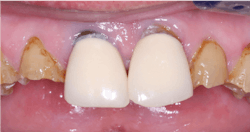

- Lithium disilicate (IPS e.max): Well-proven material, except for bruxers; consider using for single crowns (figure 3)